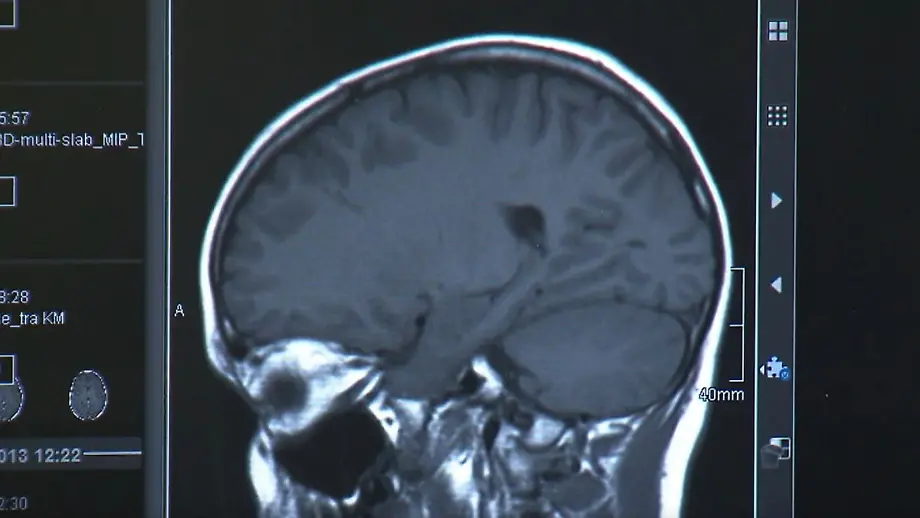

Unter anderem durch FeinstaubZahl der Parkinson-Fälle könnte drastisch steigen

12.04.2025, 15:06 UhrDas British Medicine Journal prognostiziert, dass sich die Zahl der weltweiten Parkinson-Erkrankungen in den kommenden 25 Jahren im Vergleich zu heute mehr als verdoppeln könnte. Dabei spielen neben der Überalterung von Gesellschaften auch etwa Pestizide und Feinstaub eine Rolle.